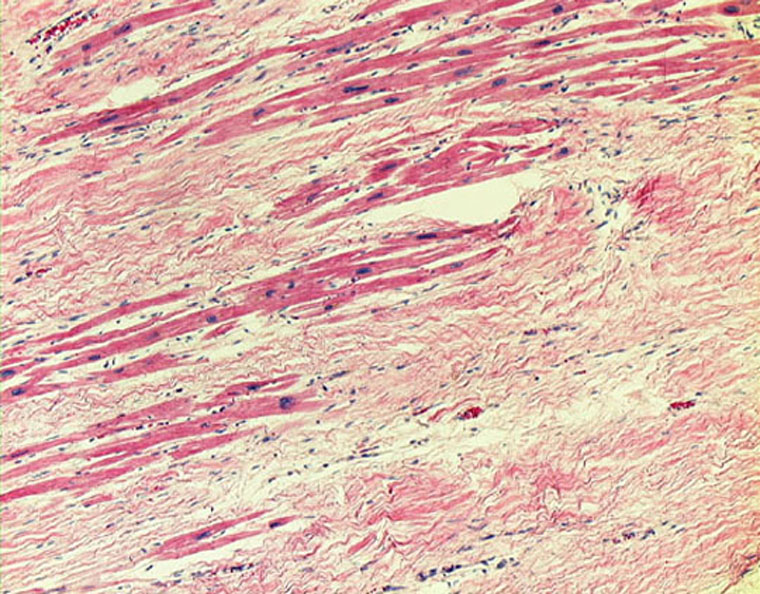

Межуточный миокардит: гистологические исследования